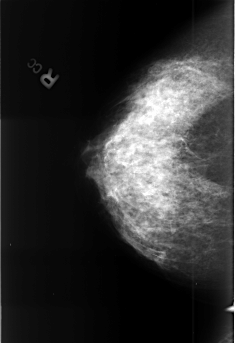

B_3390_1.RIGHT_MLO

RIGHT_CC LINES 4456 PIXELS_PER_LINE 3056 BITS_PER_PIXEL 12 RESOLUTION 50 NON_OVERLAY

RIGHT_MLO LINES 4472 PIXELS_PER_LINE 3048 BITS_PER_PIXEL 12 RESOLUTION 50 NON_OVERLAY